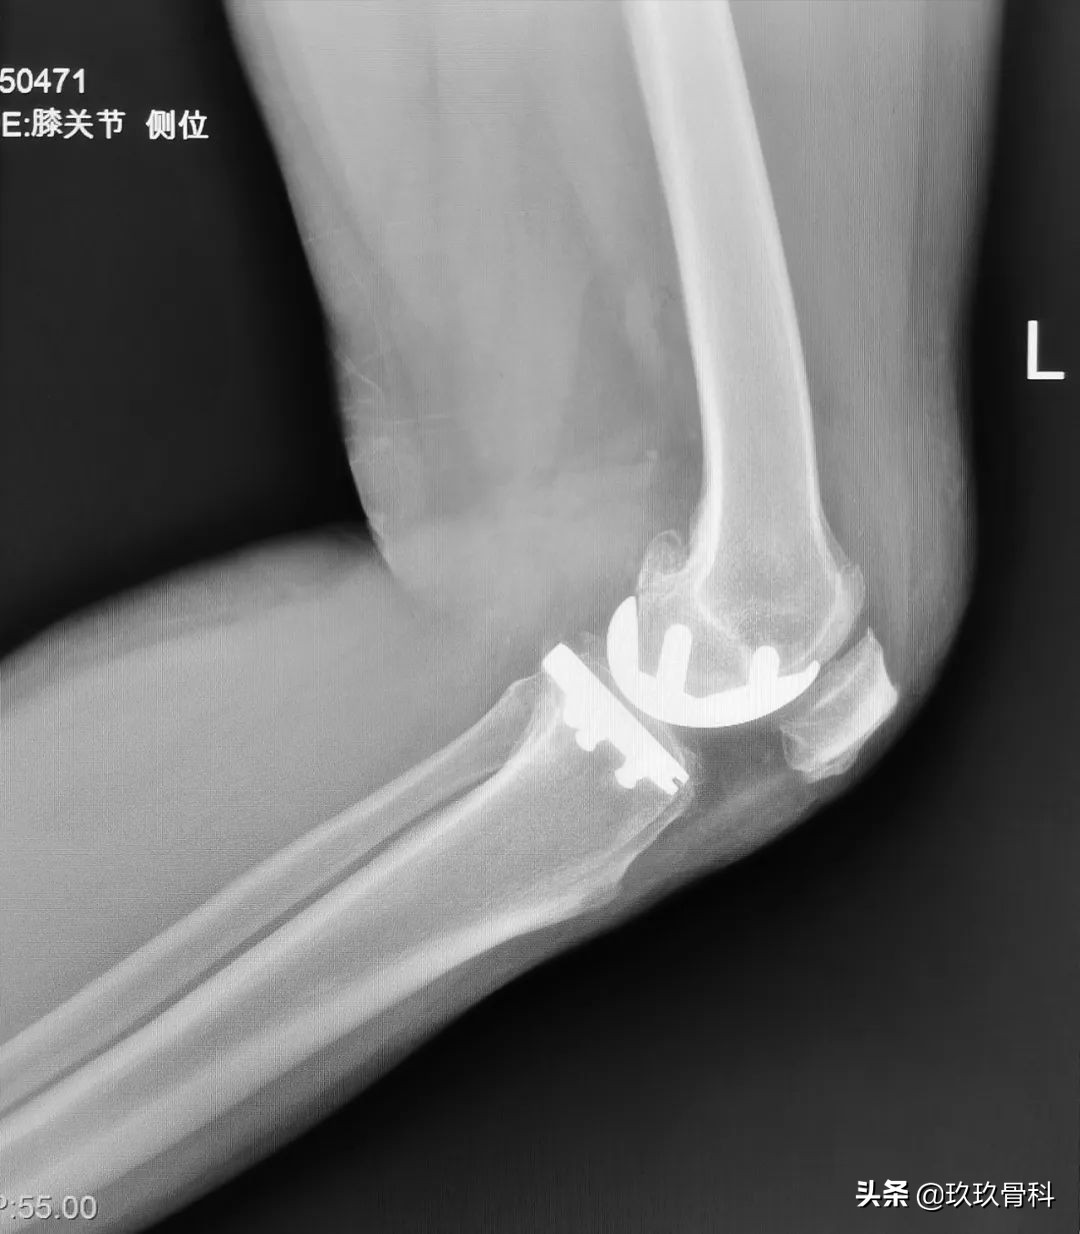

术后影像

术后第二天伸屈功能恢复良好